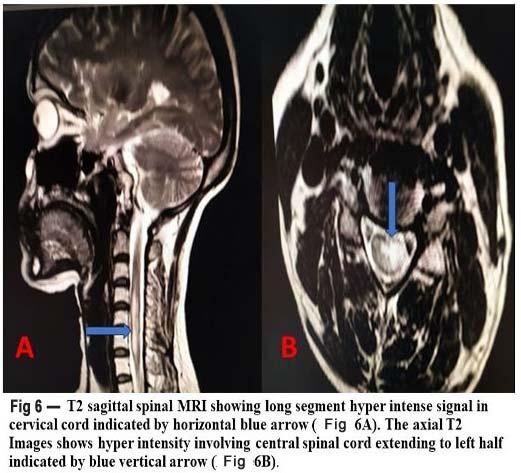

Routine blood investigations, ECG, chest Xray, CT scan and MRI of the face (including orbits) and brain were done (Fig 1).

Fig 1 — Pre-operative and Postoperative coronal MRI slice

In India till May 2020, 66.8% of the COVID-19 cases were males19. Rhino-cerebro-orbital (44-49%) was the type most commonly found, followed by cutaneous (10-19%), pulmonary (10-11%), disseminated (6-11%) and gastrointestinal (2-11%)20. But in our case study, all the cases occurring with COVID-19, diabetes and steroids led to rhino-cerebro-orbital mucormycosis. Patients usually presented with headache, fever, unilateral facial swelling, orbital cellulitis with the presence of palpebral oedema, chemosis, ptosis and ophthalmoplegia21. The prognosis is poor with about 33.3%-80% being the overall mortality rate21,22. CT scan is usually the first diagnostic tool to check the status of sinuses, although best way to detect extrasinus spread is using Magnetic Resonance Imaging (MRI)9. A definitive diagnosis of mucormycosis as the causative species is achieved only by histological examination of the biopsy specimen. Culture and KOH examination may be used only as a suggestive tool for noting the presence of mucormycosis.